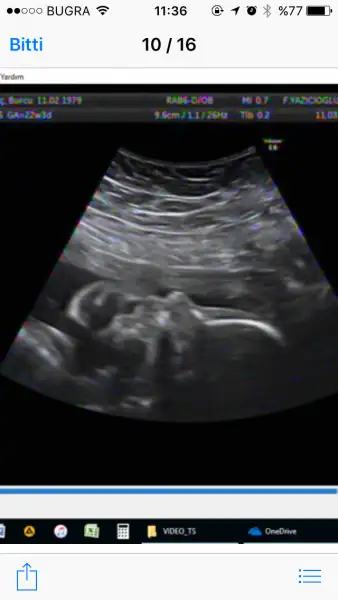

aynen canım içinde olması gerek. Bende Esenyurt Özel Esencan Hastanesine gidiyorum. 280 tl cd resim falan içinde. Ve detaylı yapan bayan o kadar tatlı ve ilgili ki kızımın net resimlerini alabilmek için en az 15 dk uğraştı ki öncesinde 20 dk kadar da bütün ayrıntılı renksiz ultrason incelemesini yaptıAyrıca fehmi bey zaten 350 tl olan muaynede dvd veya resim vermek için ayrıca 30 tl alıyor bu hizmet içinde olmalı buradan hesap etmek lazım yani olayı